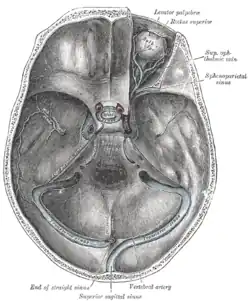

Der Sinus sagittalis superior verläuft in einer gedachten Mittellinie unter dem Schädeldach entlang der sogenannten Hirnsichel (Falx cerebri). Der Sinus sagittalis inferior verläuft im freien Rand der Falx über dem Balken und mündet zusammen mit der Vena cerebri magna in den Sinus rectus. Dieser verläuft gerade nach hinten zum Confluens sinuum, in den auch der von oben kommende Sinus sagittalis superior einmündet. Ebenfalls verbunden ist hier der Sinus occipitalis. Die paarigen Sinus transversi leiten das Blut vom Confluens weiter zur hinteren Schädelbasis, wobei sie sich im Verlauf S-förmig winden und ab dort als Sinus sigmoidei bezeichnet werden. Schließlich münden sie in die tiefen Halsvenen. Der Sinus cavernosus ist ein schwammartiges Netz, das auf dem Keilbein liegt und mit dem übrigen venösen Sinussystem durch jeweils einen Sinus petrosus superior und inferior auf jeder Seite verbunden ist.